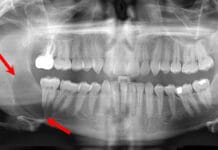

- Radiographs may be difficult for the patient. If unable to get bitewing radiographs, consider a panoramic or CBCT.